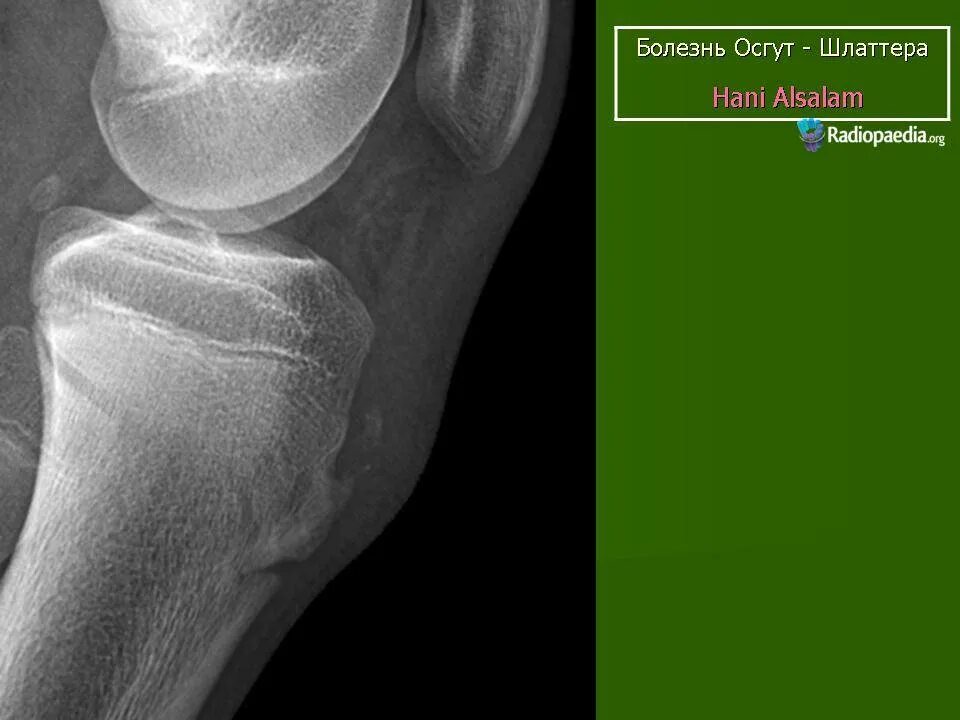

Код мкб шляттера